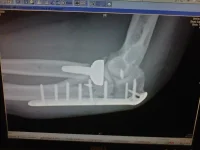

Look after yourself cause this what happened to me, not being squemish but it hurt a touch :RpS_w00t: took me over two months to even pick a pen up, ripped all the tendons off the back of my elbow i can now hold a hawk with plaster and plaster being clay of course and thats 9 months down the line...:RpS_scared: